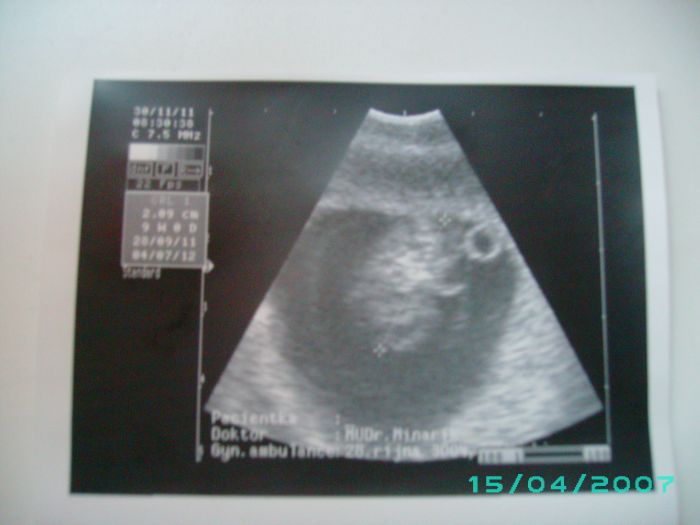

Ahojik Holky tak mam po kontrole miminko je zdrave videla jsem sredicko aj karticku jsem i dostala.Posilam Fotecku.

Moni taky mas krasne miminko no me dal dnes karticku a to jsem 9+0tt.